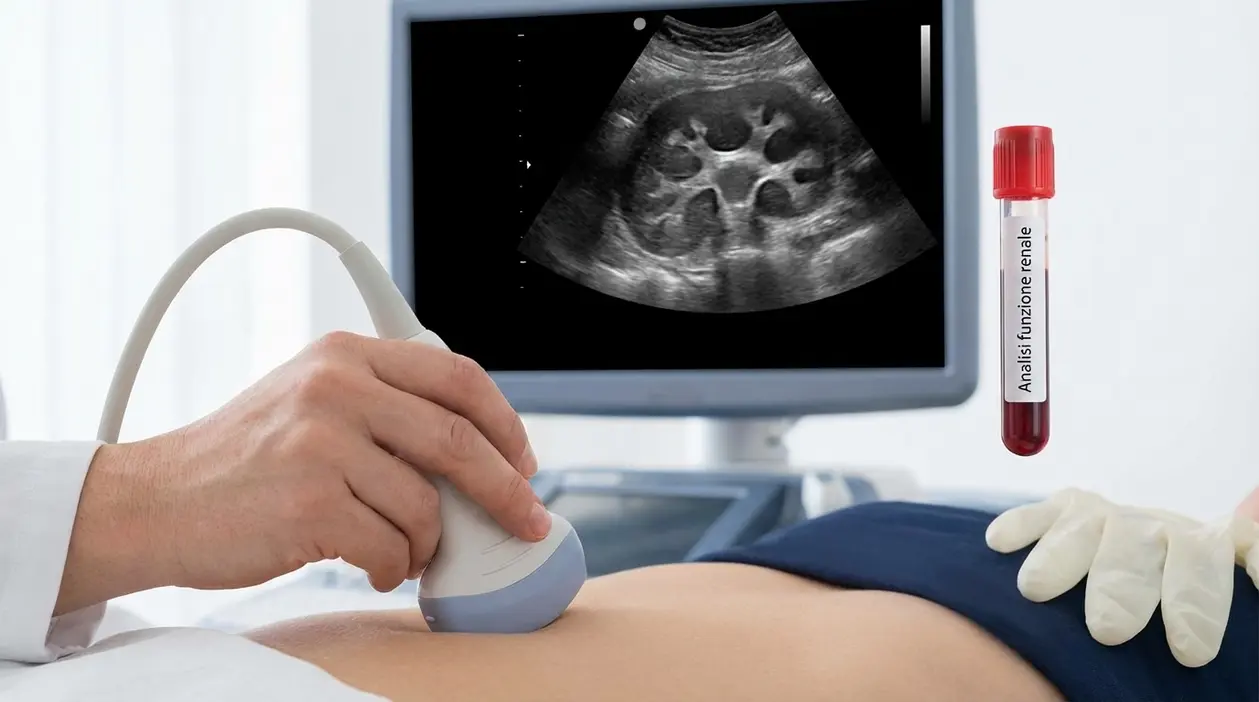

Di solito si parte dall’ecografia renale. È un esame veloce, non invasivo, e consente di capire se la pelvi renale, i calici e a volte anche l’uretere risultano dilatati. Nella pratica di tutti i giorni è spesso proprio questo esame a dare la prima vera indicazione sul da farsi.

Quando bisogna essere un po’ più precisi, il color Doppler permette di capire meglio se si tratta davvero di un megauretere oppure di una struttura vascolare lì vicino.